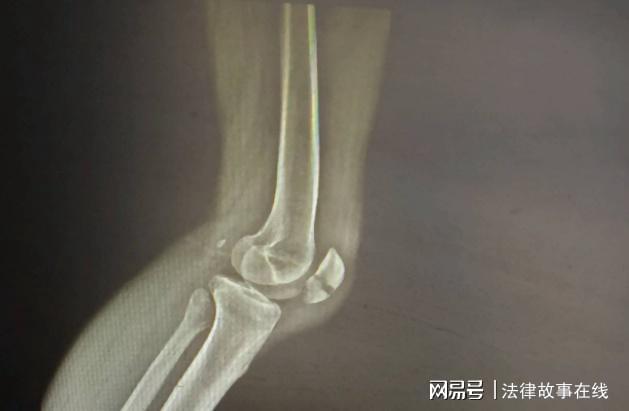

并且还造成了粉碎性骨折,于某这时什么活都干不了了,只能在家躺着,心有不甘的他决定要讨回公道,要求韩伊兵赔偿自己30万。

双方因为这件事僵住了,但是于某依然不甘心,在2020年做了一次伤情鉴定,结果显示伤情已经达到了轻伤二级,这样一来整个案件就不是简单的纠纷了。

而法院这边有证据认为,就是韩伊兵先动的手,在打斗的过程中导致于某摔倒在地,造成了摔伤,鉴定之后是轻伤二级。